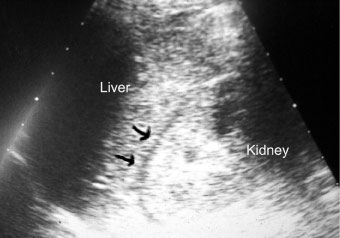

His chest radiograph demonstrated r right sided cardiac apex. His focused assessment with sonography in trauma (FAST) examination revealed the presence of fluid in Morison's pouch in the left upper quadrant (Figure 2), contusion over the spleen in the right upper side (Figure 3), but no free fluid in the pelvis or pericardial fluid. His computed tomography scan (CT) demonstrated fluid around the liver without solid liver organ injury and multiple splenic contusions (Figure 4).

Figure 2: FAST examination shows fluid in Morison's pouch (arrows). View Figure 2